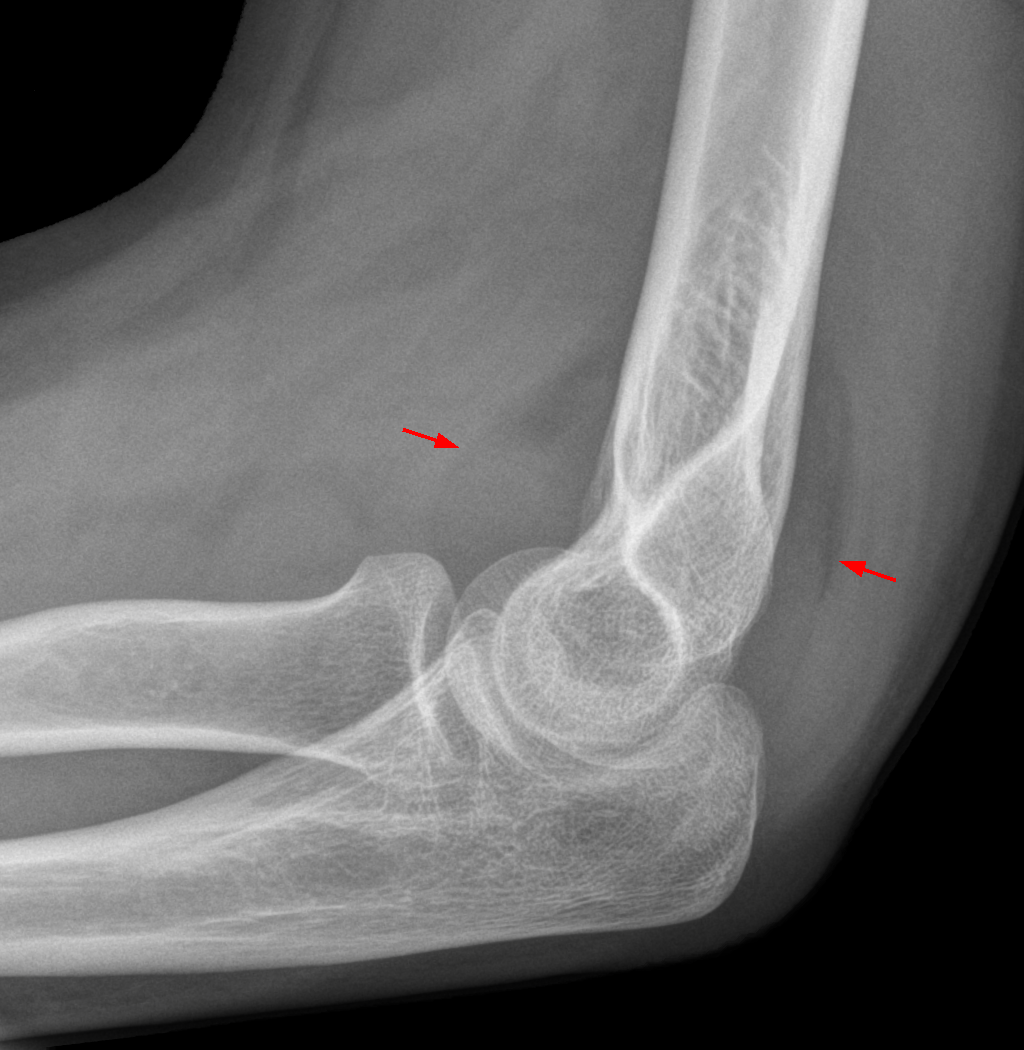

11. 팔꿈치에 있어서 후방 지방층 징후(Posterior fat pad)와 돛 징후(Sail sign)란 무엇인가?

후방 지방층 징후(Posterior fat pad)와 돛 징후(Sail sign)란 관절내 팔꿈치 골절의 존재를 암시한다. 지방은 일반적으로 활액막과 팔꿈치 관절낭 사이에 존재하는데, 원위 상완골 전방 피질에 바로 인접한 작게 투명하게 드물게 보이는 정상 전방 지방층을 제외하고는 일반적으로 방사선상으로는 보이지 않는다. 관절내 골절로 인해 나타나는 관절혈증이 활액막을 팽창시키고, 이 지방을 이동시킨다. 후방 지방층이 방사선투과형태로 보이게 되고, 전방 지방층은 삼각형의 방사선투과형태로 뼈에서부터 들어 올려진 모양으로 돛과 닮아있다.

△ Fat Pad Sign (이미지 출처 : http://en.wikipedia.org/wiki/Fat_pad_sign)